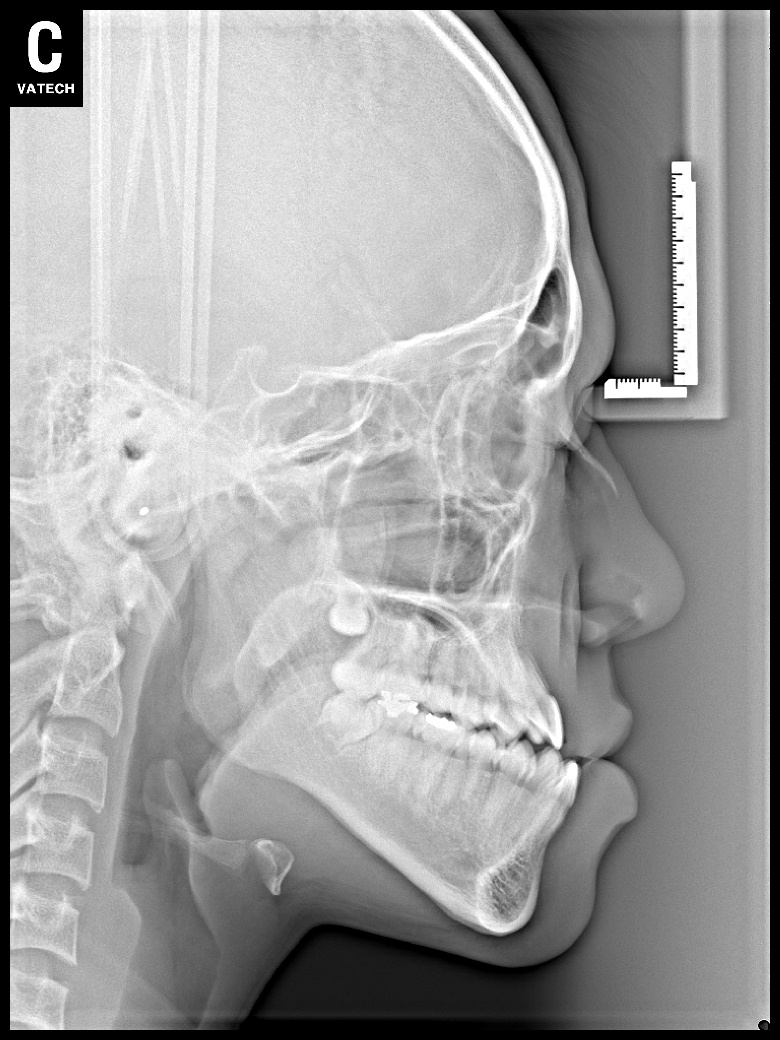

치료 후 사진입니다.